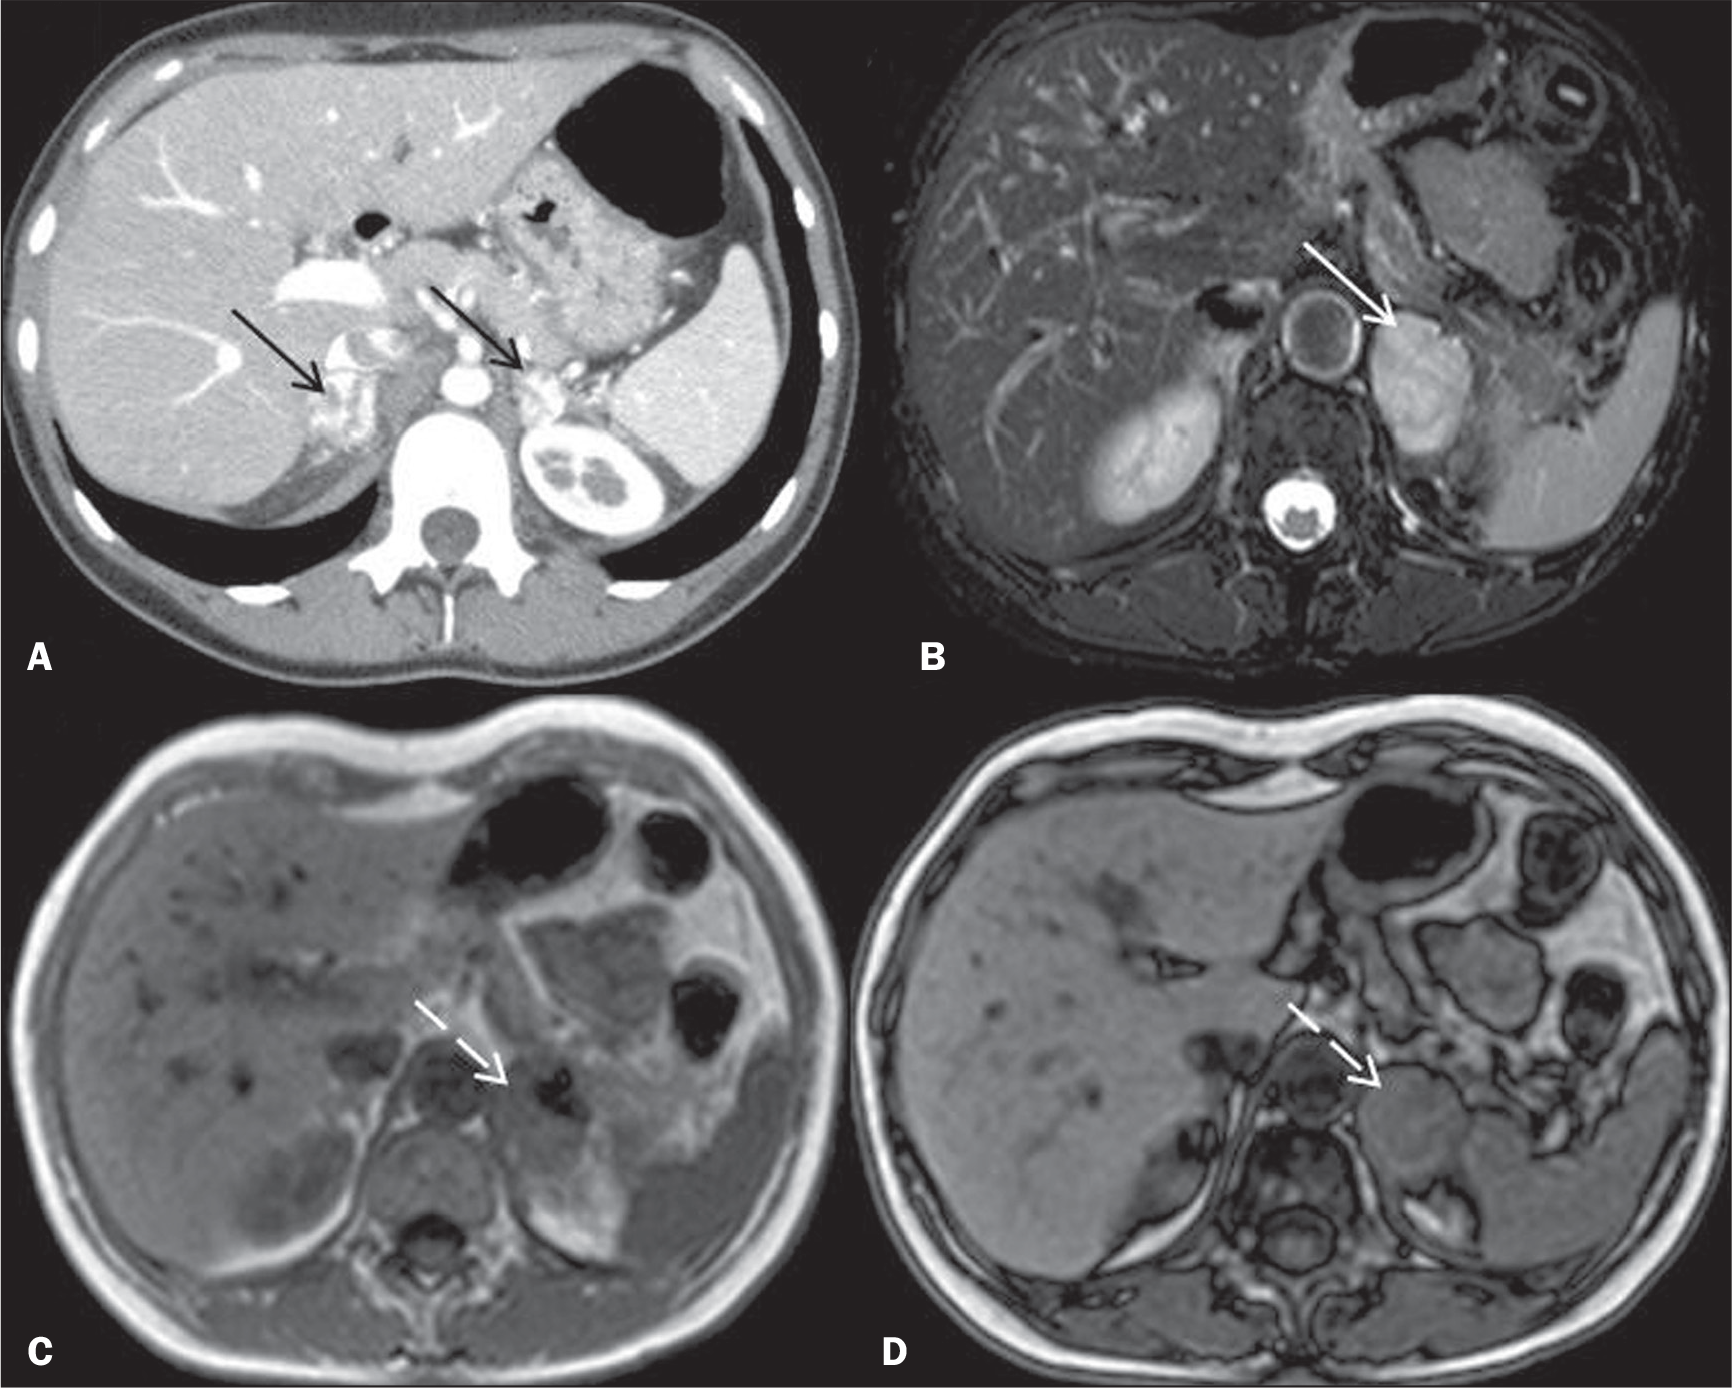

3 — Abdome (TC ou RM) — preferencialmente com contraste

- TC: fase sem contraste + fase corticomedular + fase nefrográfica.

- RM: T1, T2, difusão e pós-gadolínio (fases arterial, portal e tardia quando aplicável).

- Objetivo: identificação de carcinoma de células renais, cistos pancreáticos e tumores neuroendócrinos.